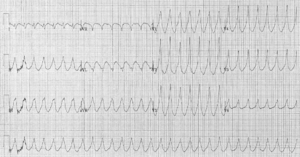

Electrocardiogram

The primary purpose of the electrocardiogram is to detect ischemia or acute coronary injury in broad, symptomatic emergency department populations. However, the standard 12 lead ECG has several limitations. An ECG represents a brief sample in time. Because unstable ischemic syndromes have rapidly changing supply versus demand characteristics, a single ECG may not accurately represent the entire picture. It is therefore desirable to obtain serial 12 lead ECGs, particularly if the first ECG is obtained during a pain-free episode. Alternatively, many emergency departments and chest pain centers use computers capable of continuous ST segment monitoring. The standard 12 lead ECG also does not directly examine the right ventricle, and is relatively poor at examining the posterior basal and lateral walls of the left ventricle. In particular, acute myocardial infarction in the distribution of the circumflex artery is likely to produce a nondiagnostic ECG. The use of additional ECG leads like right-sided leads V3R and V4R and posterior leads V7, V8, and V9 may improve sensitivity for right ventricular and posterior myocardial infarction. In spite of these limitations, the 12 lead ECG stands at the centre of risk stratification for the patient with suspected acute myocardial infarction. Mistakes in interpretation are relatively common, and the failure to identify high risk features has a negative effect on the quality of patient care.

The 12 lead ECG is used to classify patients into one of three groups:

- those with ST segment elevation or new bundle branch block (suspicious for acute injury and a possible candidate for acute reperfusion therapy with thrombolytics or primary PCI),

- those with ST segment depression or T wave inversion (suspicious for ischemia), and

- those with a so-called non-diagnostic or normal ECG.

A normal ECG does not rule out acute myocardial infarction. Sometimes the earliest presentation of acute myocardial infarction is the hyperacute T wave, which is treated the same as ST segment elevation. In practice this is rarely seen, because it only exists for 2-30 minutes after the onset of infarction. Hyperacute T waves need to be distinguished from the peaked T waves associated with hyperkalemia. The current guidelines for the ECG diagnosis of acute myocardial infarction require at least 1 mm (0.1 mV) of ST segment elevation in the limb leads, and at least 2 mm elevation in the precordial leads. These elevations must be present in anatomically contiguous leads. (I, aVL, V5, V6 correspond to the lateral wall; V1-V4 correspond to the anterior wall; II, III, aVF correspond to the inferior wall.) This criterion is problematic, however, as acute myocardial infarction is not the most common cause of ST segment elevation in chest pain patients. Over 90% of healthy men have at least 1 mm (0.1 mV) of ST segment elevation in at least one precordial lead. The clinician must therefore be well versed in recognizing the so-called ECG mimics of acute myocardial infarction, which include left ventricular hypertrophy, left bundle branch block, paced rhythm, early repolarization, pericarditis, hyperkalemia, and ventricular aneurysm.

Left bundle branch block and pacing interferes with the electrocardiographic diagnosis of acute myocadial infarction by making the ST segment uninterpretable. The GUSTO investigators Sgarbossa et al. developed a set of criteria for identifying acute myocardial infarction in the presence of left bundle branch block and paced rhythm. They include concordant ST segment elevation > 1 mm (0.1 mV), discordant ST segment elevation > 5 mm (0.5 mV), and concordant ST segment depression in the left precordial leads. The presence of reciprocal changes on the 12 lead ECG may help distinguish true acute myocardial infarction from the mimics of acute myocardial infarction. The contour of the ST segment may also be helpful, with a straight or upwardly convex (non-concave) ST segment favoring the diagnosis of acute myocardial infarction.

The constellation of leads with ST segment elevation enables the clinician to identify what area of the heart is injured, which in turn helps predict the so-called culprit artery.

As the myocardial infarction evolves, there may be loss of R wave height and development of pathological Q waves (defined as Q waves deeper than 1 mm and wider than 1 mm.) T wave inversion may persist for months or even permanently following acute myocardial infarction. Typically, however, the T wave recovers, leaving a pathological Q wave as the only remaining evidence that an acute myocardial infarction has occurred.